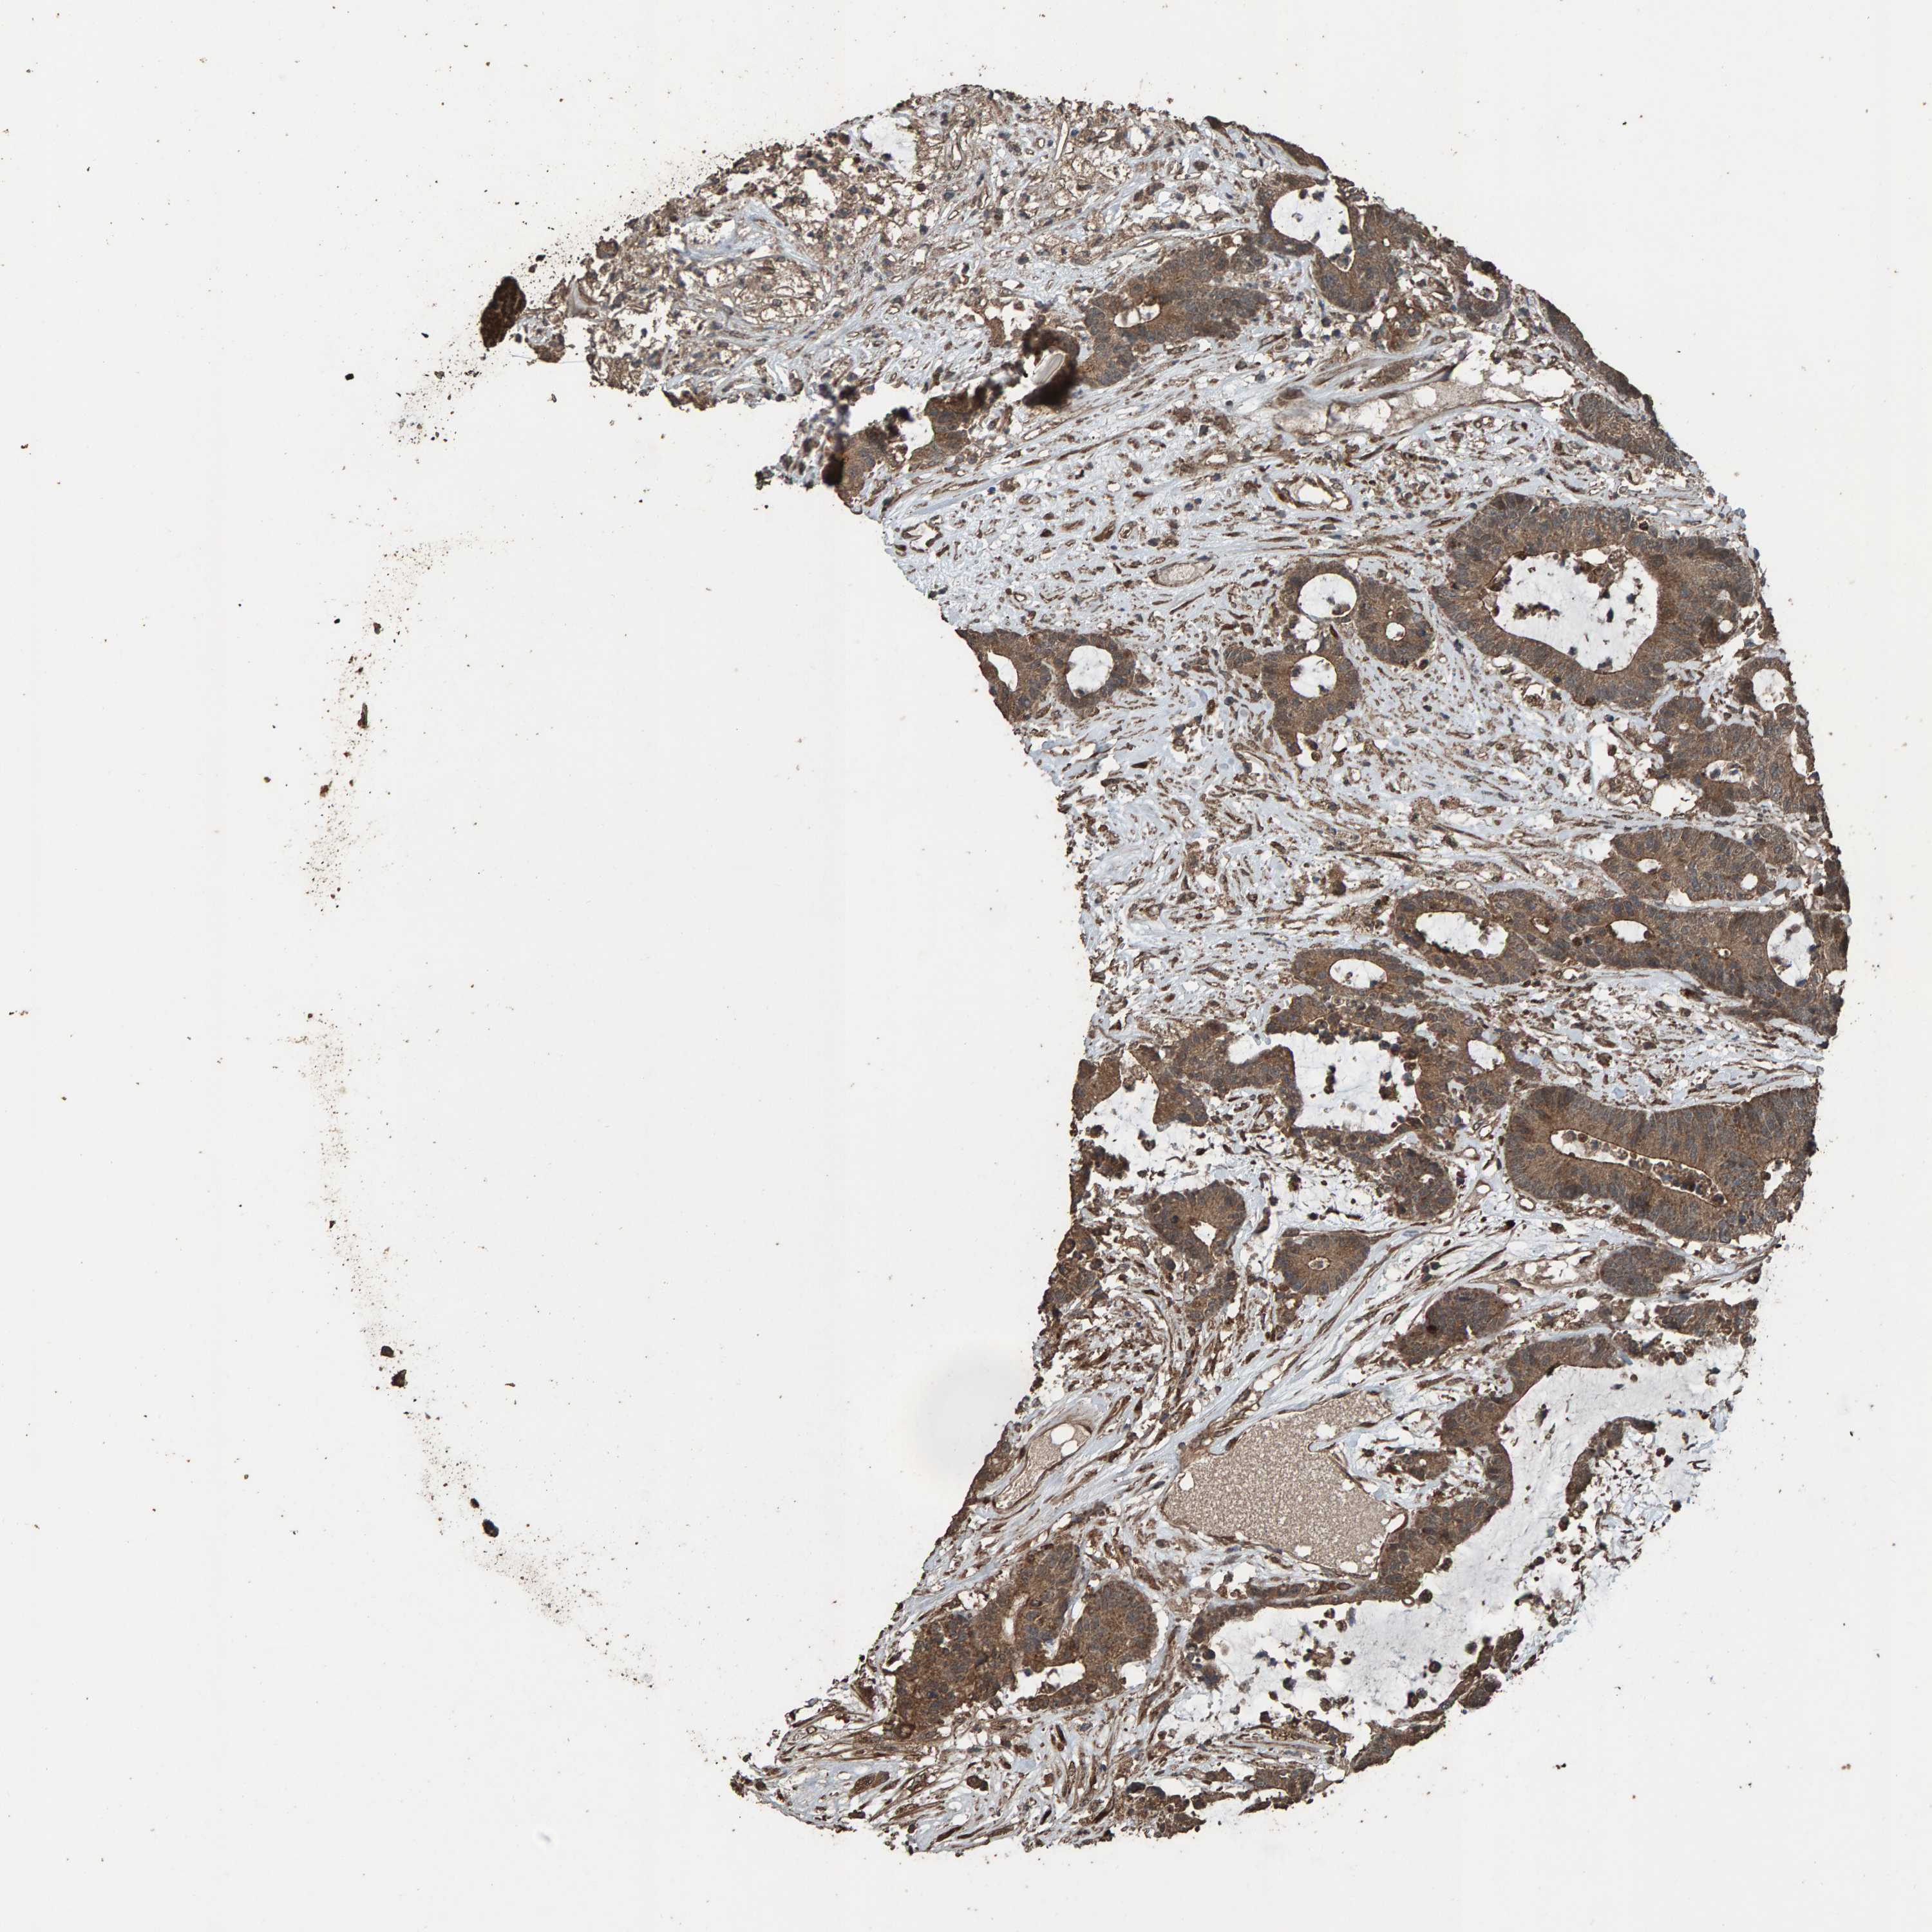

Colorectal cancer

Colon adenocarcinoma

COLON ADENOCARCINOMA (VALIDATION) - Interactive survival scatter ploti

The Survival Scatter plot shows the clinical status (i.e. dead or alive) for all individuals in the patient cohort, based on the same data that underlies the corresponding Kaplan-Meier plots. Patients that are alive at last time for follow-up are shown in blue and patients who have died during the study are shown in red.

The x-axis shows the expression levels (FPKM) of the investigated gene in the tumor tissue at the time of diagnosis. The y-axis shows the follow-up time after diagnosis (years). Both axes are complimented with kernel density curves demonstrating the data density over the axes. The top density plot shows the expression levels (FPKM) distribution among dead (red) and alive patients (blue). The right density plot shows the data density of the survived years of dead patients with high and low expression levels respectively, stratified using the cutoff indicated by the vertical dashed line through the Survival Scatter plot. This cutoff is automatically defined based on the FPKM cutoff that minimizes the p-score. The cutoff can be changed by dragging the vertical line or by entering a cutoff value in the square labeled "Current cut-off".

Under the Survival Scatter plot the p-score landscape (black curve; left axis) is shown together with dead median separation (red curve; right axis). Dead median separation is the difference in median mRNA expression between patients who have died with high and low expression, respectively. It is calculated as follows: median FPKM expression of dead patients with high expression - median FPKM expression of dead patients with low expression. This is intended to aid the user in visually exploring custom cutoffs and the associated p-scores and dead median separation.

Individual patient data is displayed and can be filtered by clicking on one or more of the category buttons on the top of the page. Categories describing expression level and patient information include: high, low, alive, dead, female, male and tumor stages. The scale of the x-axis can be toggled between linear and log-scale by clicking on the "x log" button. Mouse-over function shows TCGA ID, patient information and mRNA expression (FPKM) for each patient.

& Survival analysisi

Kaplan-Meier plots summarize results from analysis of correlation between mRNA expression level and patient survival. Patients were divided based on level of expression into one of the two groups "low" (under cut off) or "high" (over cut off). X-axis shows time for survival (years) and y-axis shows the probability of survival, where 1.0 corresponds to 100 percent.

DUS1L is not prognostic in Colon Adenocarcinoma (validation)

Current cut offi

Current cut-off shows the cut-off (FPKM) currently selected. It may be changed manually. When the current cut-off is changed, the vertical dashed line indicating cut-off, the interactive survival scatter plot and the Kaplan-Meier curve will be automatically adjusted to show results accordingly.

Best expression cut offi

Based on the FPKM value of each gene, patients were classified into two groups and association between prognosis (survival) and gene expression (FPKM) was examined. The best expression cut-off refers the FPKM value that yields maximal difference with regard to survival between the two groups at the lowest log-rank P-value. Best expression cut-off was selected based on survival analysis .

When clicking on this number, the vertical dashed line indicating cut-off, the interactive survival plot, and the Kaplan-Meier curve will be adjusted to show results based on the best expression cut-off.

: 79.32

Median expressioni

Median expression refers to the median FPKM value calculated based on the gene expression (FPKM) data from all patients in this dataset. When clicking on this number, the vertical dashed line indicating cut-off, the interactive survival plot, and the Kaplan-Meier curve will be adjusted to show results based on the median expression.

: N/A

Median follow up timei

Median follow up time refers to the median time (years) after diagnosis with this type of cancer, based on clinical data from all patients in this dataset.

P scorei

Log-rank P value for Kaplan-Meier plot showing results from analysis of correlation between mRNA expression level and patient survival.

N/A

5-year survival highi

5-year survival for patients with higher expression than the expression cutoff.

For melanoma and glioma, 3-year survival is shown.

5-year survival lowi

5-year survival for patients with lower expression than the expression cutoff.

TCGA RNA samplesi

RNA-seq data is reported as average FPKM (number Fragments Per Kilobase of exon per Million reads), generated by the The Cancer Genome Atlas (TCGA) .

Normal distribution across the dataset is visualized with box plots, shown as median and 25th and 75th percentiles. Points are displayed as outliers if they are above or below 1.5 times the interquartile range. FPKM values of the individual samples are presented next to the box plot.

Average pTPM 94.2

Number of samples 486